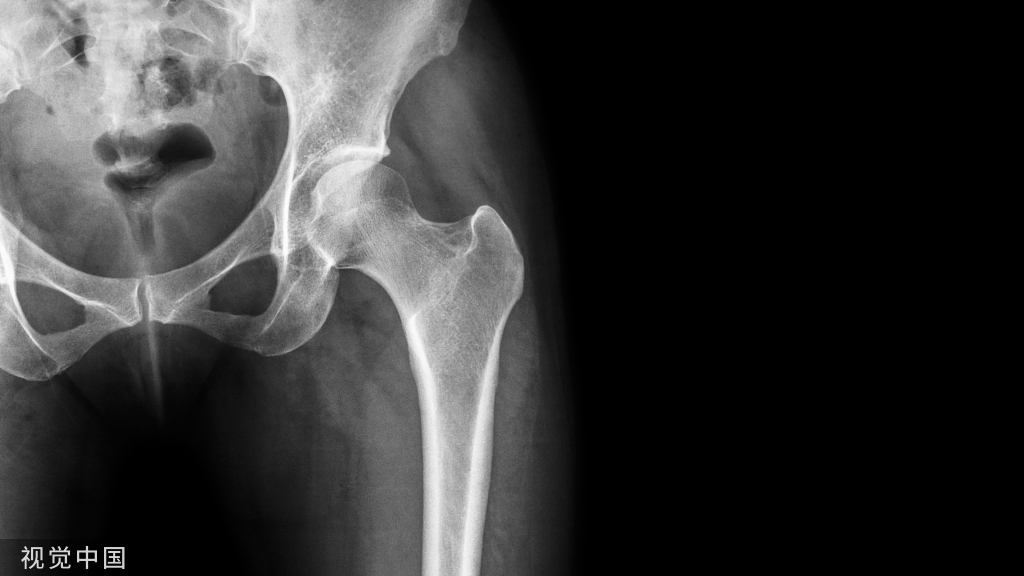

STEP 3:取骨区的选择与处理

1、自体骨移植取骨部位

2、不同取骨区的特点 皮质骨---较多骨形成蛋白(BMP),细胞成分少,成活较困难,成活后吸收少。

• 松质骨---富含细胞成分,疏松结构有利于新血管生长,较易成活,吸收较多。